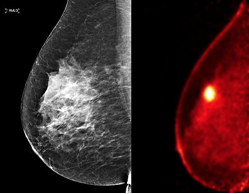

Mammogram

Mammogram: Simply put, a mammogram is a type of X-ray that allows you to view below the surface of your breast. Today, it is a common practice for women above the age of 40 to undergo annual digital mammography. So, if post the physical breast checkup, the doctor suspects that you may have a tumour/lumps/abnormalities, they may request a mammogram.

Also, remember that your mammogram may show breast calcifications which are nothing but calcium deposits within the breast tissue. It is a common phenomenon and is especially prevalent for women after age 50.